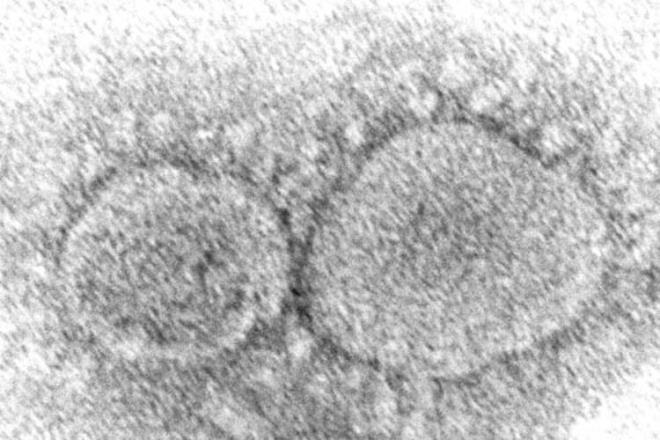

1. DSÖ Genel Direktörü Tedros Adhanom Ghebreyesus, korona virüs salgınının son durumuna yönelik basın toplantısı düzenledi. Ghebreyesus konuşmasında, "77 ülke şu anda Omicron vakaları bildirdi ve gerçek şu ki Omicron henüz tespit edilmemiş olsa bile muhtemelen çoğu ülkede bulunuyor. Omicron, daha önce hiçbir mutasyonda görmediğimiz bir oranda yayılıyor" dedi.

2. İnsanların Omicron'u hafife almasından endişe duyduğunu belirten Ghebreyesus, Omicron'un hafife alınmaması gerektiğini vurguladı. Ghebreyesus, "Omicron daha az ciddi hastalığa neden olsa bile çok sayıda vaka, hazırlıksız sağlık sistemlerini bir kez daha zor duruma sokabilir" ifadelerini kullandı.